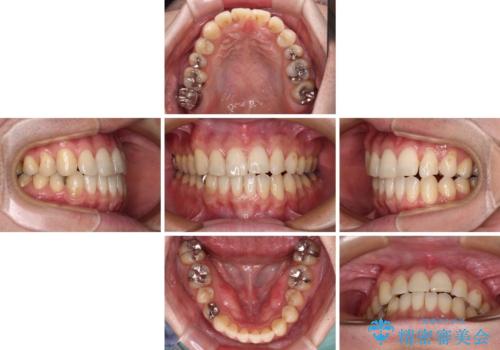

インビザライン矯正は、1日22時間を目安に装着する必要がありますが、しっかりと装着してくださったので、順調に治療を進めることができました。

- 1年10ヶ月

- 10-30回